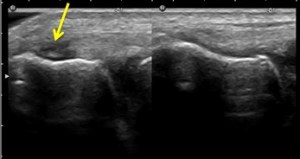

I usually perform a bedside ultrasound examination to confirm the diagnosis.

During ultrasound examination, I look for hypoechogenic areas in the common extensor tendon. This implies an area of tendon substance degeneration. Occasionally I can detect focal areas of calcifications. It is also good to examine the contralateral pain free elbow to look for differences.